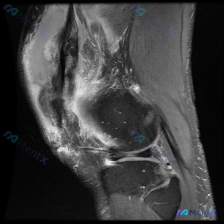

看到这例膝关节MRI,整理一下影像发现和分析思路,和大家一起讨论。 病例影像基本信息 这是一例膝关节轴位T2加权MRI图像,涵盖股骨髁间窝、髌股关节及周围软组织,具体影像发现如下: 1. 骨骼结构:股骨远端骨皮质及骨松质信号未见明显异常 2. 关节软骨:髌骨关节面软骨不均匀高信号、边缘轮廓模糊;股骨...